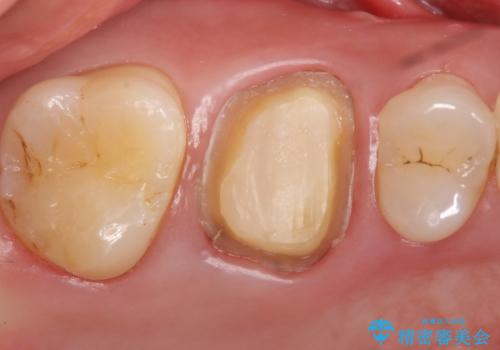

- 見た目が気になるため右上6のゴールドクラウンをセラミックにしたいといらっしゃった方の症例です。

再根管治療を御希望されたため根管治療を行った後、メタルボンドクラウンによる補綴を行いました。